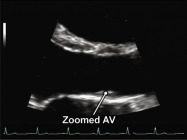

| 2.3. Mặt cắt trục dài cạnh ức phóng đại van động mạch chủ

Cửa sổ siêu âm cạnh ức

Mặt cắt trục dài cạnh ức Đặt hộp phóng đại vào vị trí van động mạch chủ, đường ra thất trái, động mạch chủ lên Chùm siêu âm đặt vuông góc với cấu trúc và có thể đặt đầu dò lên các khoang liên sườn cao hơn nếu cần. |

Van động mạch chủ (AV) | |||||